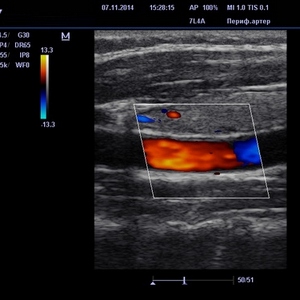

- Цветовой метод. Позволяет определить состояние сосудов и качество кровотока. Венозная сеть отображается синим оттенком, артериальная – красным цветом.